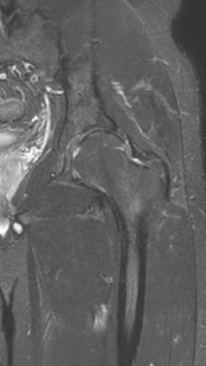

Асептический некроз тазобедренного сустава

3 процедуры ФДТ, 9 процедур MBST, 20 процедур ИПМТ

Параметры изменяются в зависимости от процедуры